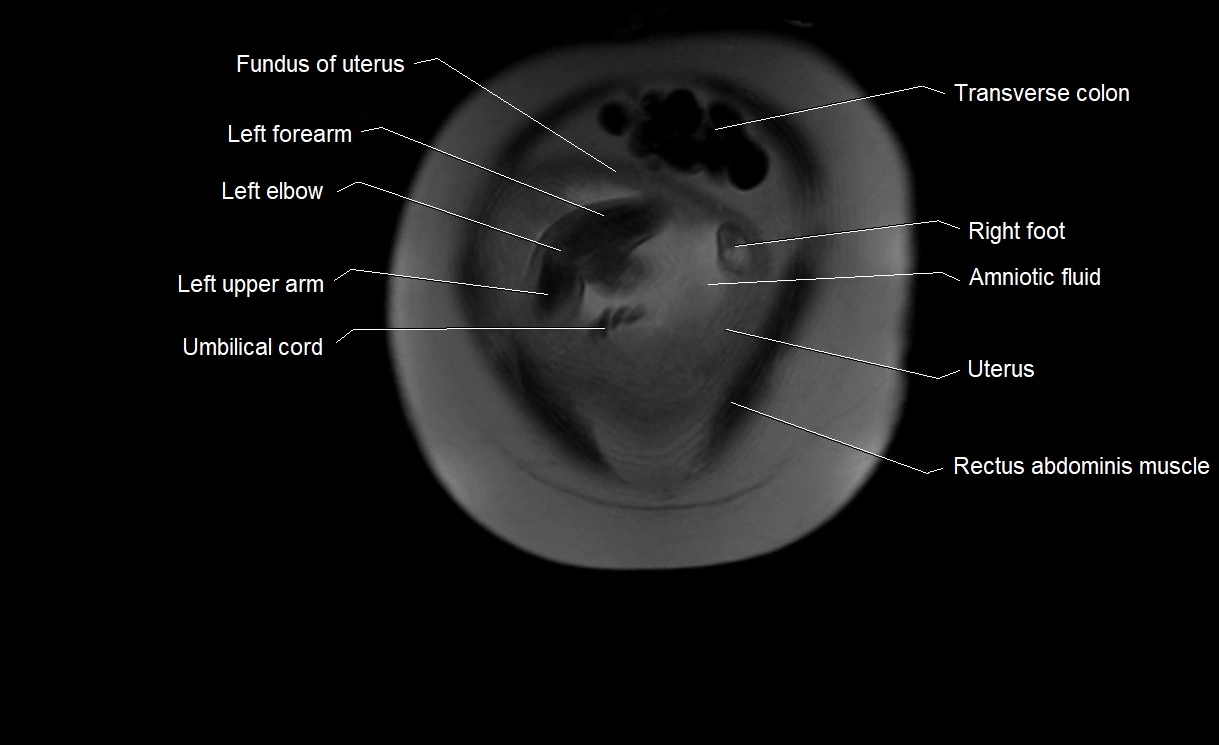

MRI Appearance

T2 HASTE (T2 GRE):

• Amniotic fluid shows very bright hyperintense signal

• Provides natural contrast against fetus and placenta

• Small particles (vernix) may appear as scattered hypointense foci within bright fluid

MRI image

image